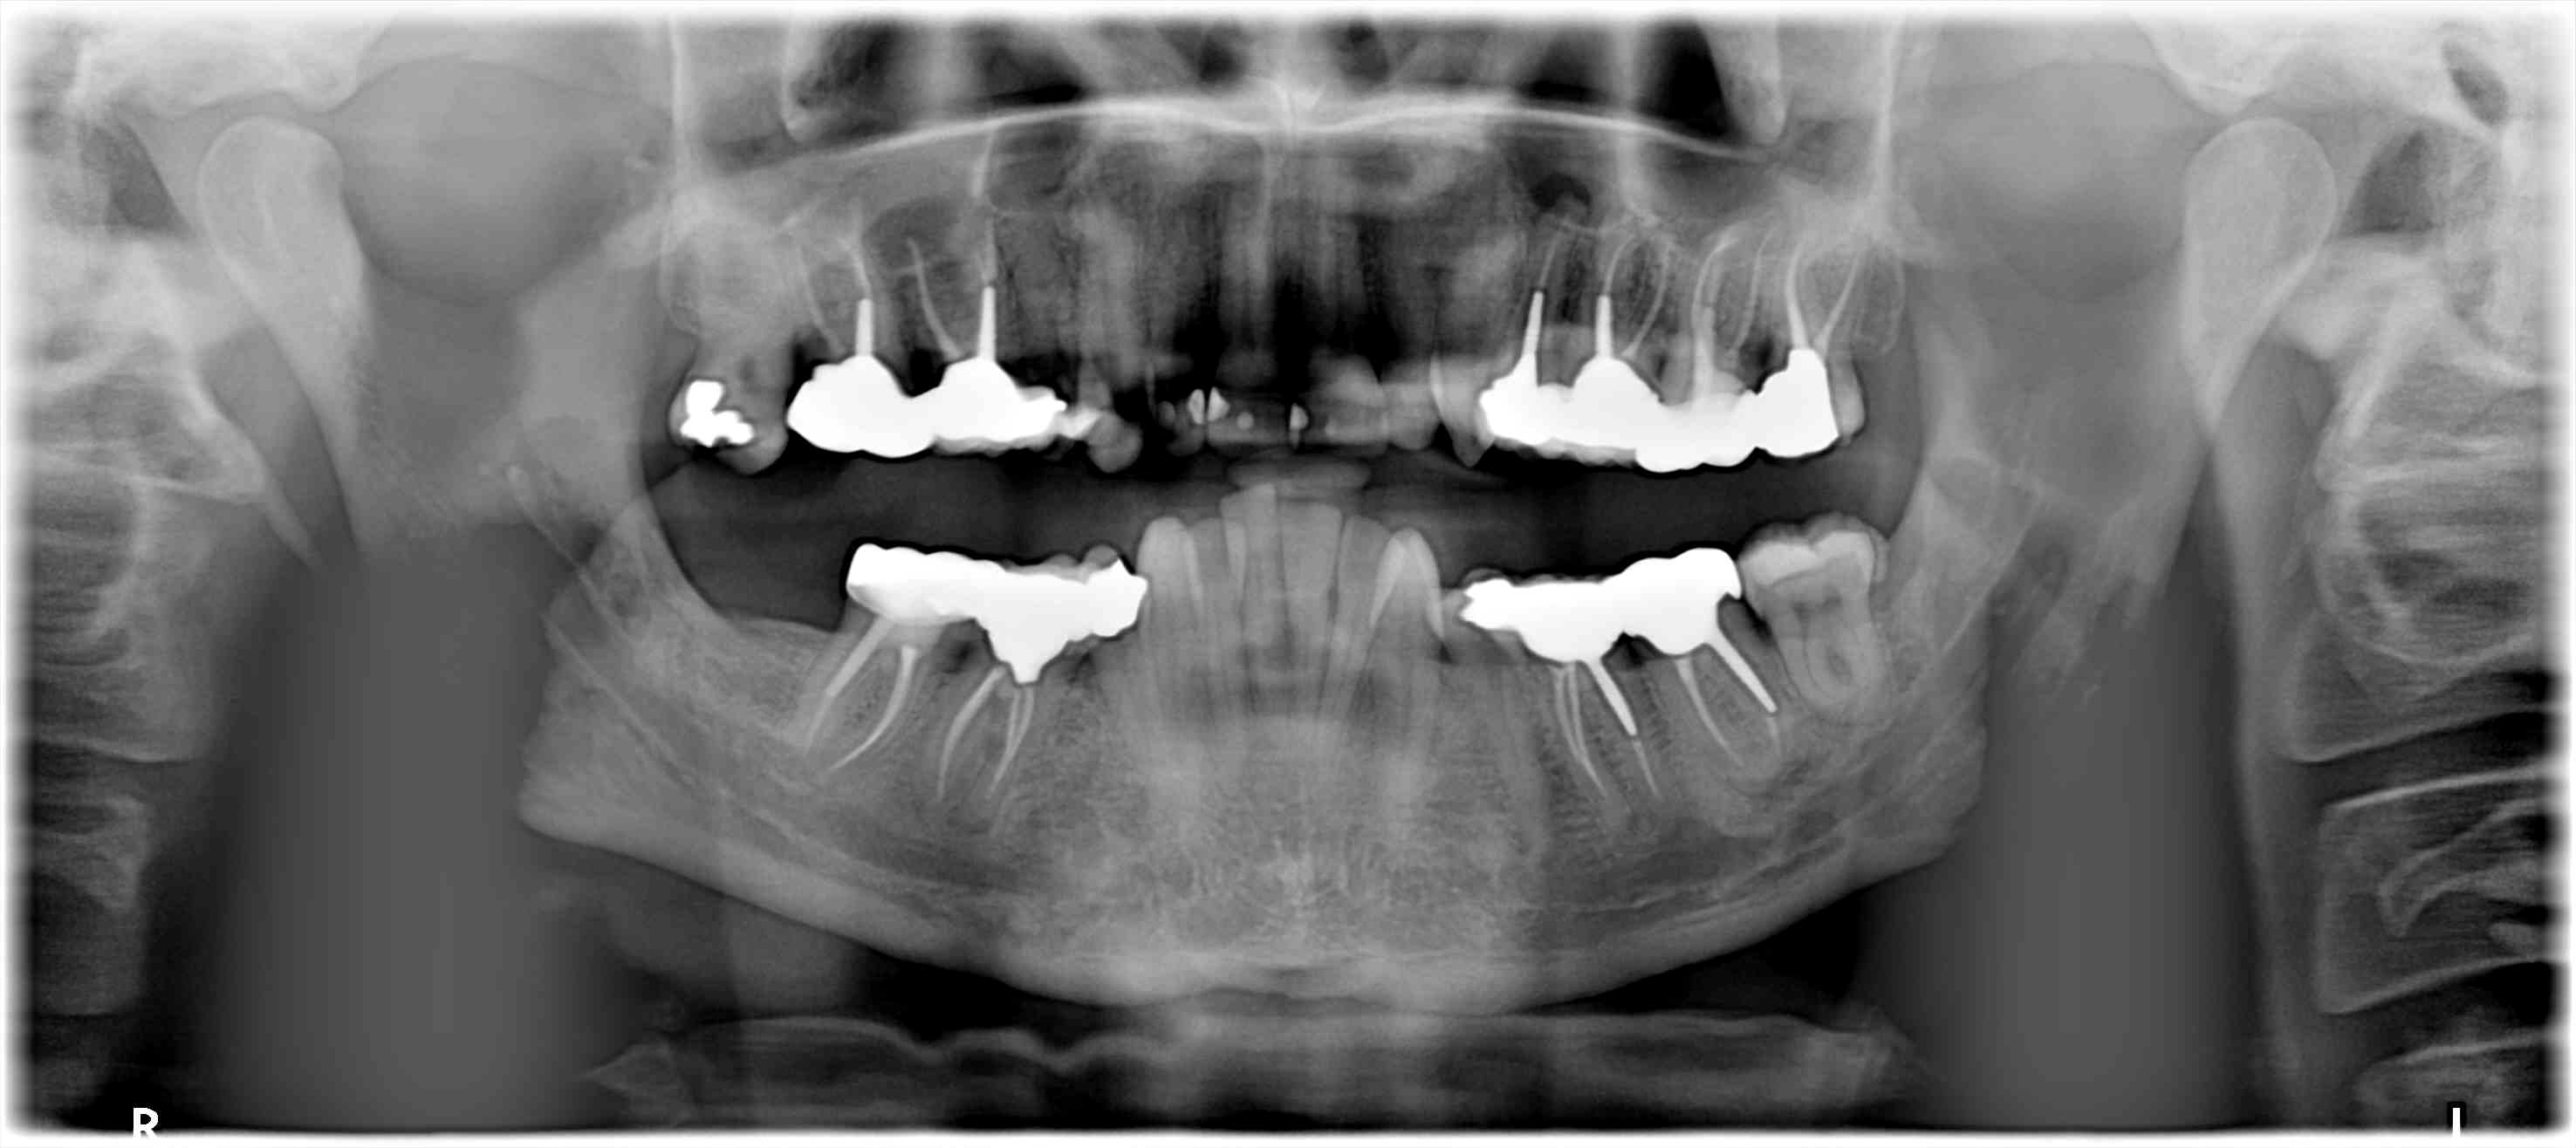

un patient consulte pour un bilan avant ortho Invasilign.

La pano montre une lésion sur 24, 46, traitement canalaire ancien.

La lésion sur 46 minime, (je laisse), la 24 (' RTT+chir apicale) mais découverte d'une lésion sur la 36. Que feriez-vous ?

Sorry, c'est la 37, qui me chagrine , pas la 36....